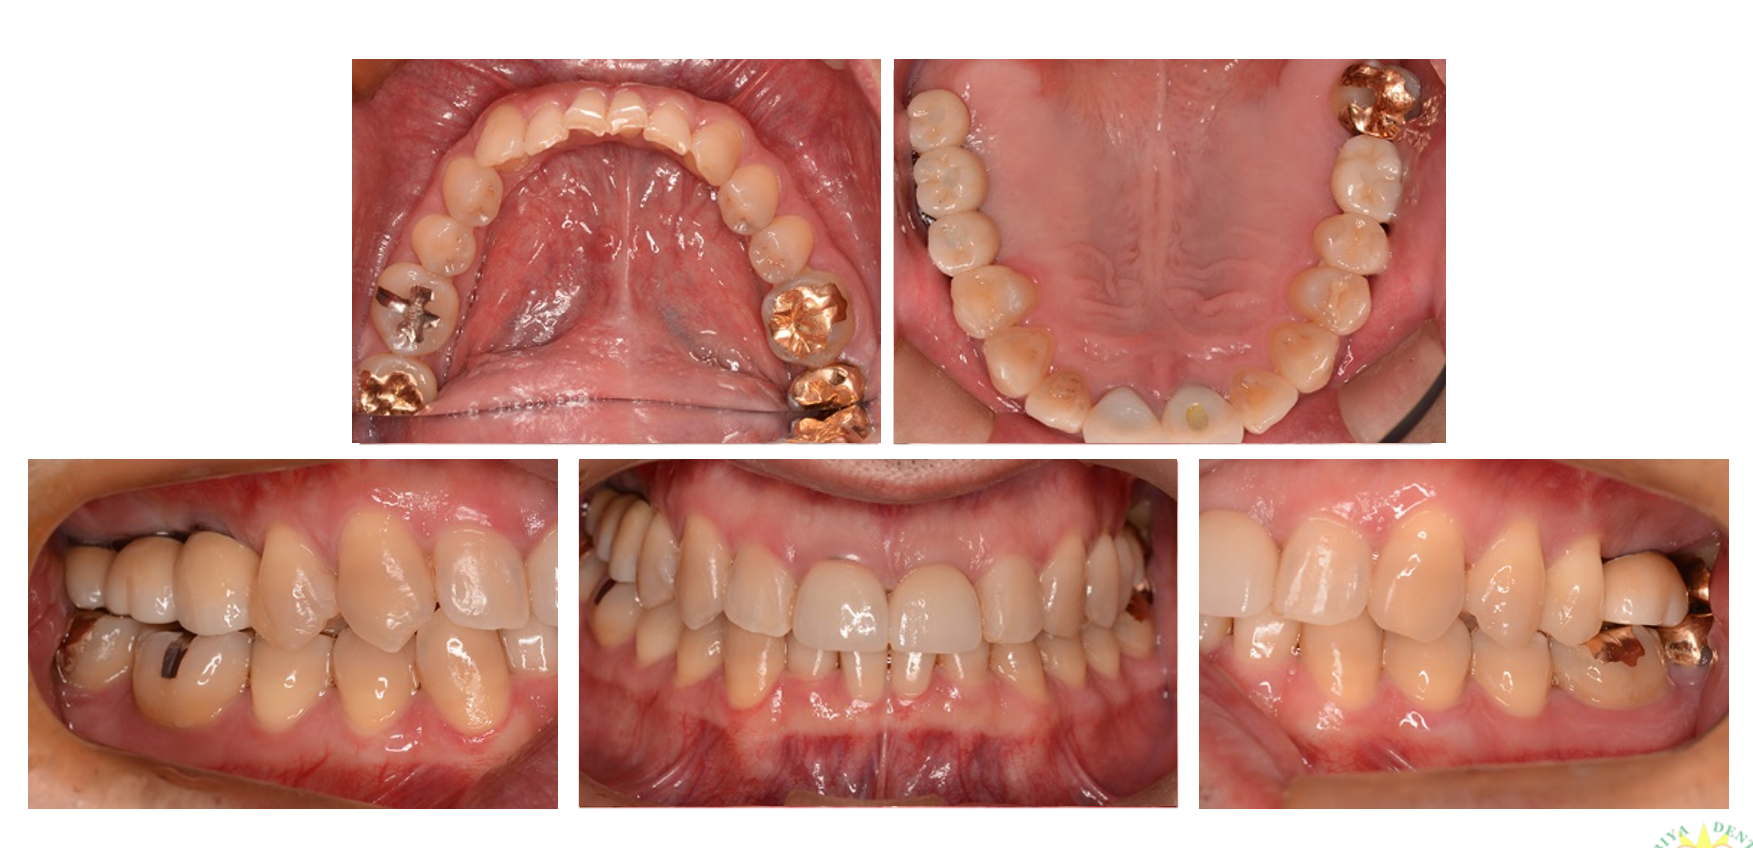

インプラント治療の症例4

(前歯の歯根破折)

| 診断名・主訴 | 左上1歯根破折 |

| 年齢 | 39歳 |

| 治療期間 | 1年間 |

| 治療内容 | インプラント治療 |

| 治療に用いた主な材料、設備機器 | 京セラFINESIAインプラント 上部構造:ジルコニアセラミック |

| 抜歯部位 | 左上1 |

| 治療費 | 約50万円 |

| リスク・副作用 | 術後出血や腫れ |